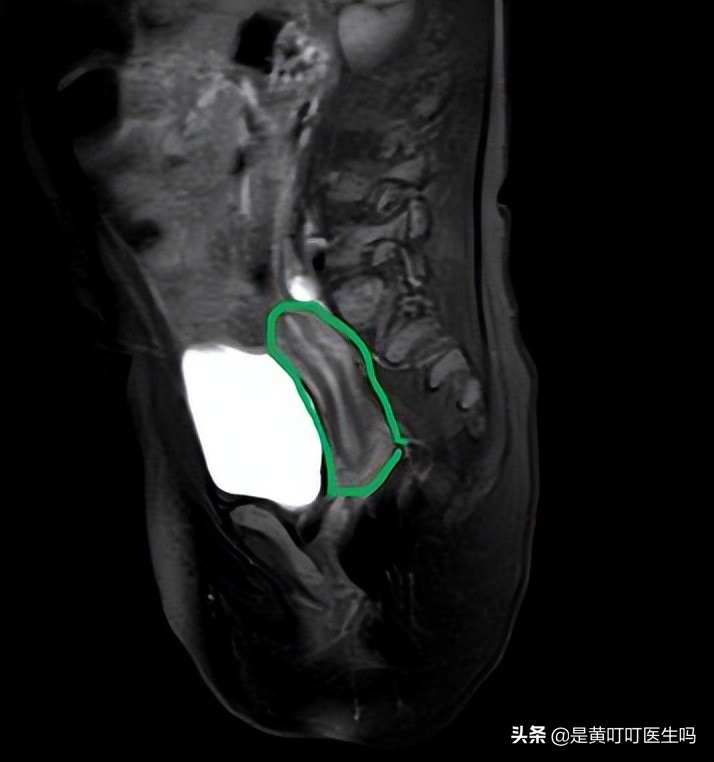

宝宝的子宫、卵巢、阴道确实也提前发育了。

子宫提前发育

卵巢提前发育